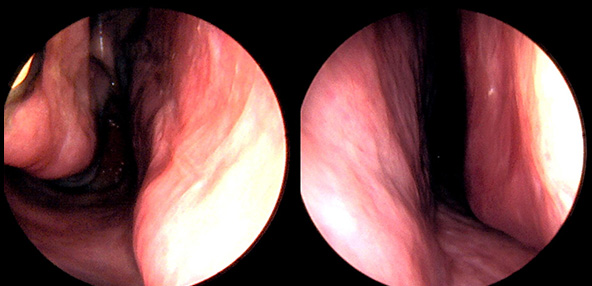

본 사진은 의료기관에서 진료를 본 환자이고, 전후 사진 인물이 동일인이며,동일조건에서 촬영이 되었습니다.